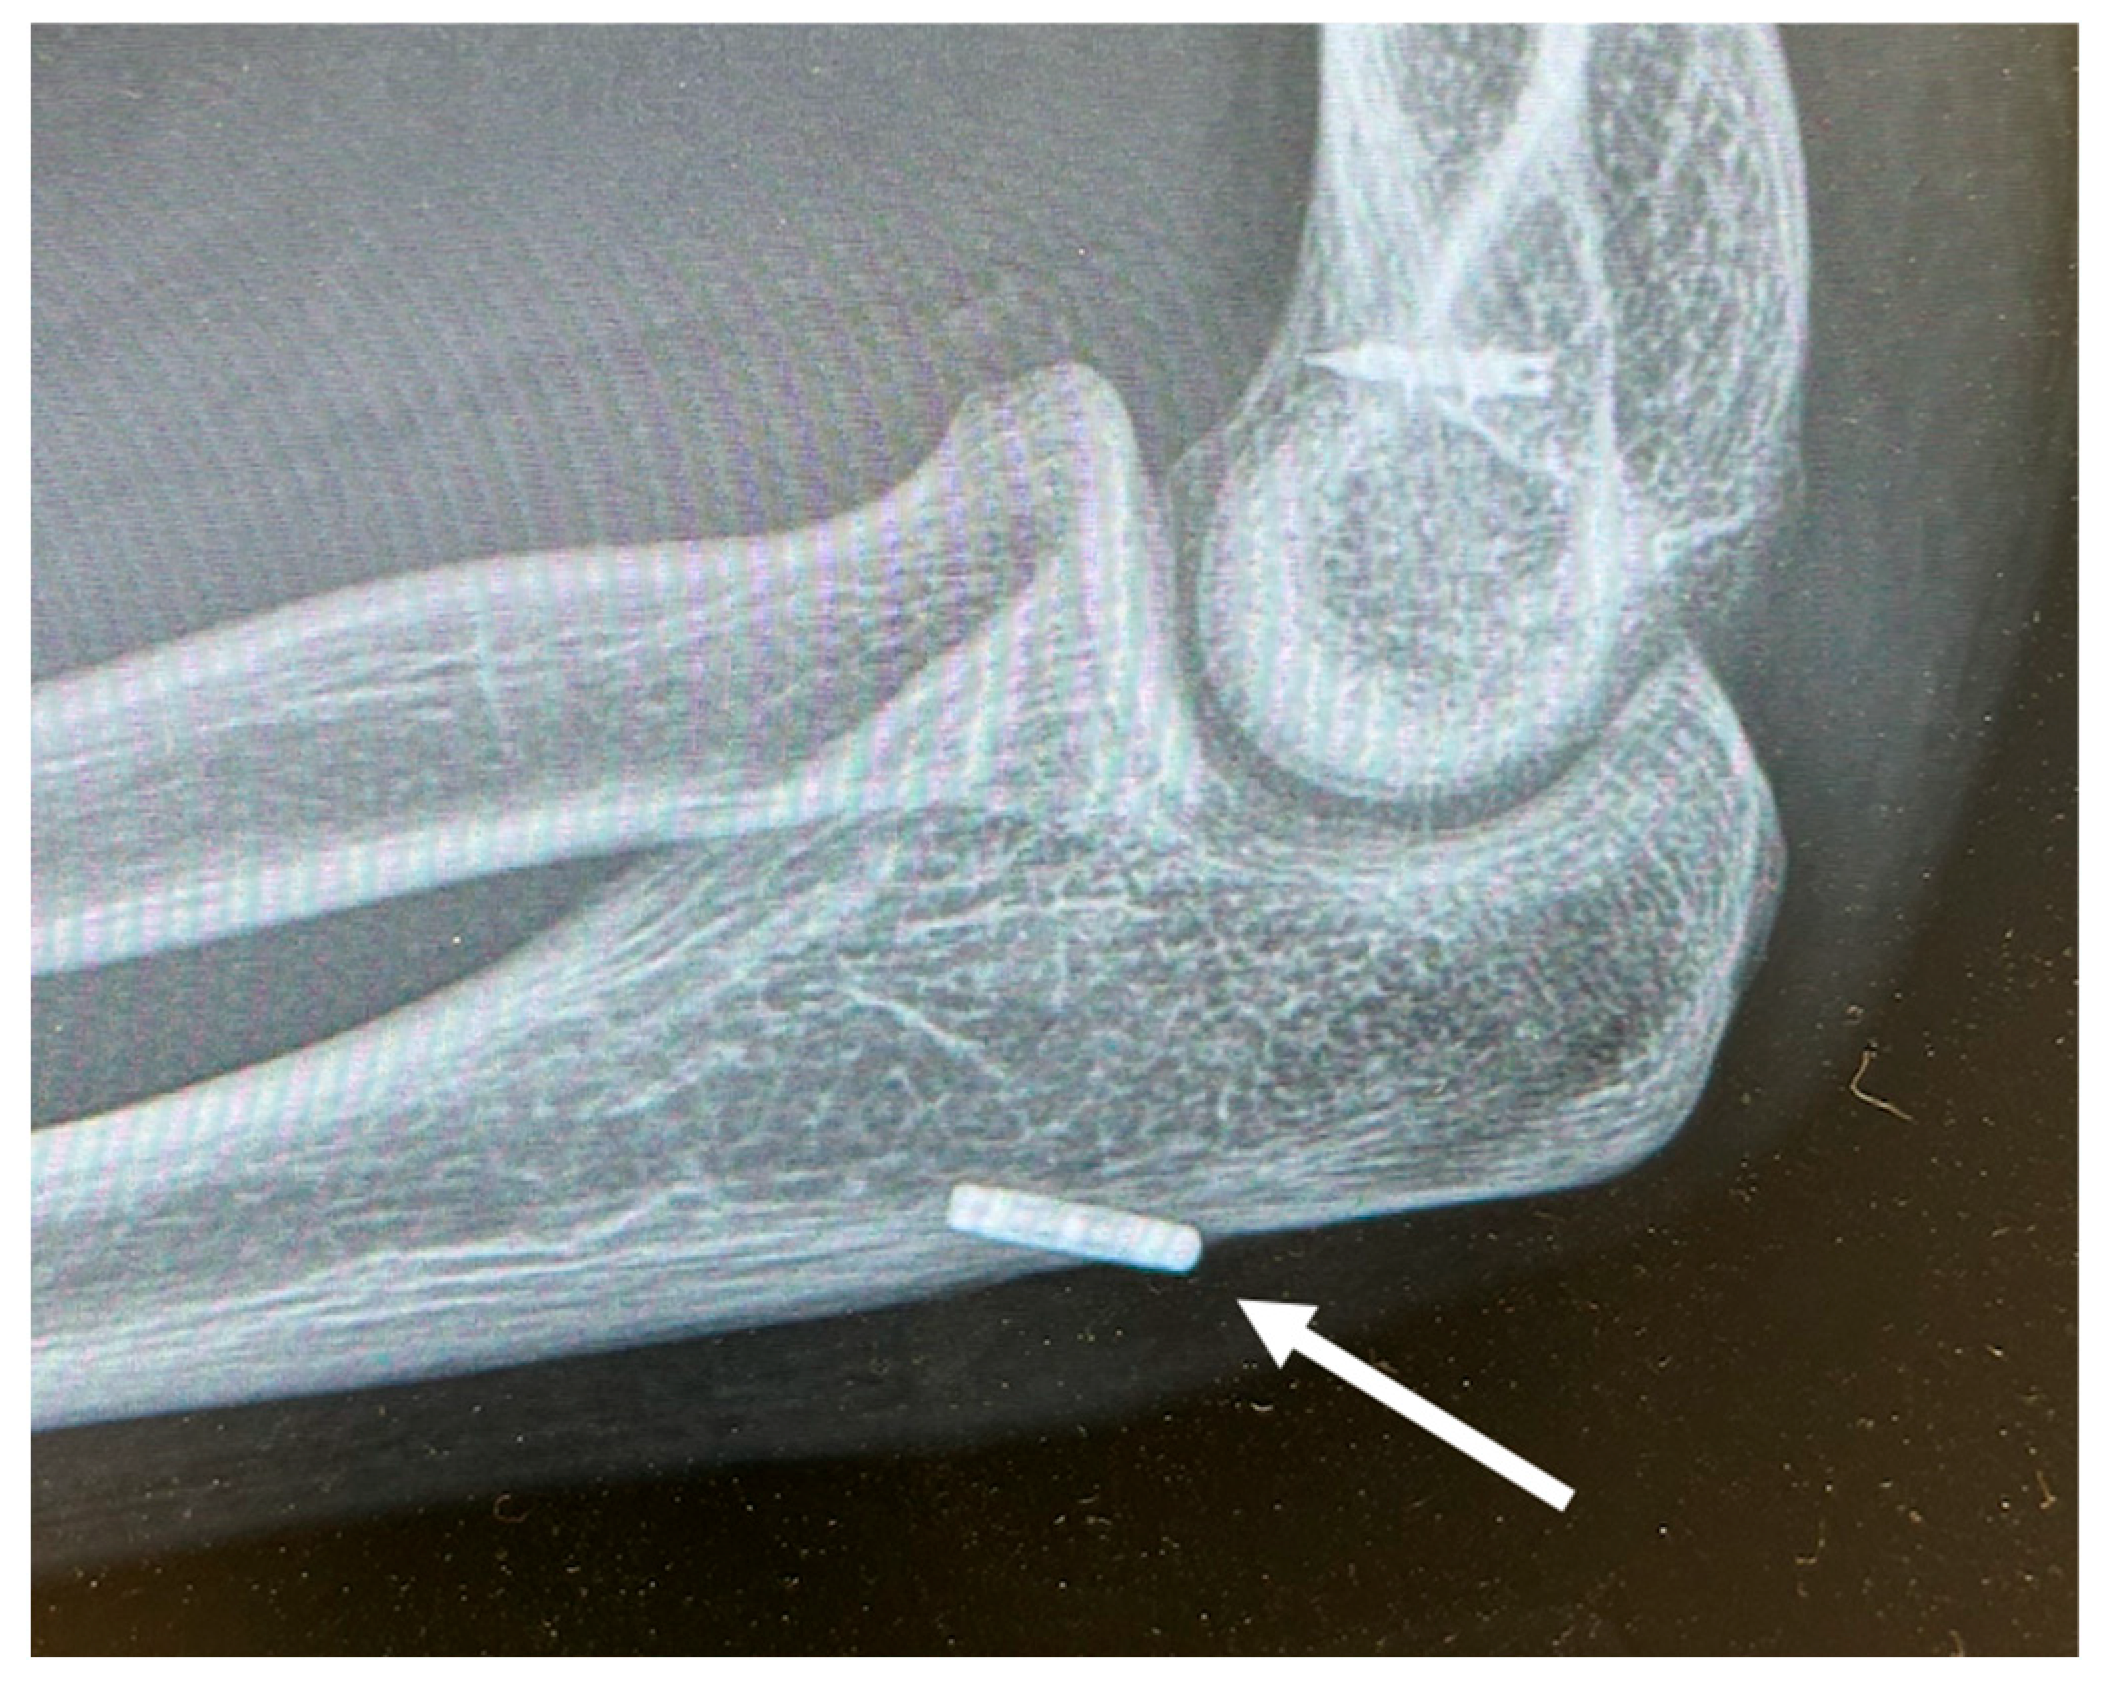

In an effort to improve the strength of suture fixation, other methods have been developed that incorporate small anchoring devices. Cortical button fixation is one strategy that has been effectively utilized in other areas of orthopaedic surgery. A similar technique, the “screw post” construct, secures the suture limbs to a cortical screw placed in the proximal ulna. For this construct, the cortical screw can be placed independently, acting solely as a post, or serve as a secondary method of fixation for a large coronoid fragment. This technique has been effective in the management of ligamentous reconstructions, such as those of the anterior cruciate ligament (ACL) [6,7]. The purpose of this study was to compare the biomechanical strengths of three different techniques for anterior capsule and coronoid fixation: bone tunnel, screw-post construct (Figure 1), and cortical suture button (Figure 2).

Figure 2. Lateral elbow radiograph demonstrating capsular repair using the suture suspension technique with a cortical button, which is represented by the arrow.